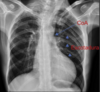

A: edema alveolar B: líneas B de Kerley C: cardiomegalia D: dilatación de vasos en lóbulos superiores E: derrame pleural

130

Insuficiencia cardiaca